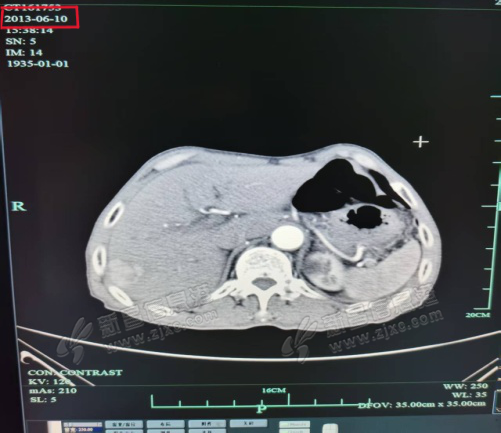

近日,一位九十岁高龄的患者在新昌县人民医院医共体沃洲分院顺利完成影像学复查。这已是老人接受肝癌介入微创治疗后连续第十二年的年度随访。复查结果再次证实:其肝内肿瘤病灶已完全灭活,未见任何复发或转移迹象。 ...